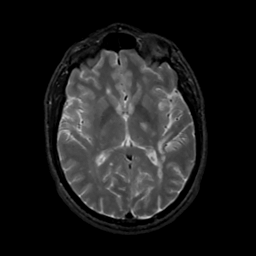

MR Study #8, March 31, 1991 -- Slice #26